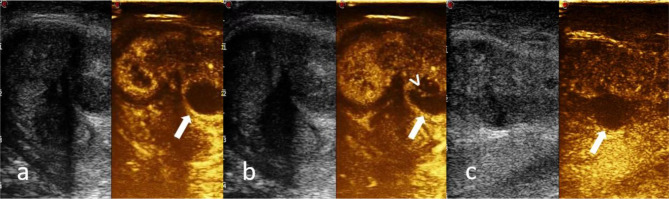

Fig. 3.

a–c CEUS shows a marginal rim enhancement in the arterial phase persistent in the tardive one (arrow), enhancement of the septa (arrowhead) and no perfusion of the necrotic areas